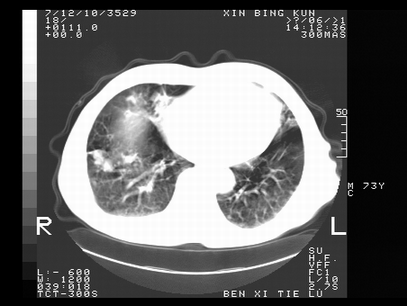

标题: CT10820:男,73岁,病史肺TB,现病史肺炎,直肠CA术后 [打印本页]

标题: CT10820:男,73岁,病史肺TB,现病史肺炎,直肠CA术后

双肺间质改变,依据病史双肺多发结节灶考虑转移,少量胸水.

1.两肺结核.2.两肺多发转移瘤.3右侧少量胸腔积液4.主动脉钙化.

双肺多发结节及条片状致密影,右侧少量胸腔积液。临床:直肠ca术后,肺tb病史。综合考虑:1 双肺转移!2 继发性肺结核合并感染!

此人病史较复杂,原有肺结核,直肠癌术后。肺部病灶形态亦呈多形性。因此,不可仅以一种病来解释肺部的病变。双肺多发的类圆形结节灶,结合病史还是首先考虑转移瘤,而双肺其余病灶还需结合化验室检查,结核或肺部感染在无其它检查资料的情况下不好排除。还是那句话----放射科医生不是开照像馆的,我们也是医生,看片一定要多结合临床及其它检查资料。要当一名合格的放射科医生,并不比当一名临床医生容易,我们可别把自已不当医生看。

两肺多发结节影,并见滋养动脉与其相连,考虑 两肺转移. 右侧胸腔积液考虑胸膜转移.

左肺上叶下叶背段,右肺中下叶见多发斑片状、条索状高密度影,兵变周围小结节影形成“树芽”样改变。 左肺上叶舌段近前胸壁处及右肺中叶内侧段见结节影。右侧胸膜腔内见液体密度区。纵隔内未见明确增大淋巴结。考虑左肺上叶舌段近前胸壁处及右肺中叶转移瘤可能性大。两肺继发型肺结核。右侧胸腔积液。